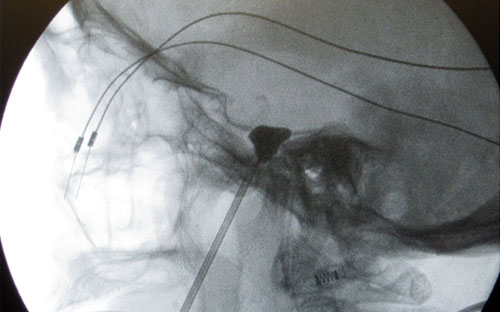

En este procedimiento la interrupción del nervio es por compresión mecánica del ganglio con un balón. La punción del ganglio es igual a la descrita arriba, a través de la aguja de punción se introduce una catéter que lleva un globo en la punta y que se infla dentro del ganglio con una mezcla de suero y contraste radiológico (total 1 cc) y se mantiene la compresión de uno a cuatro minutos.